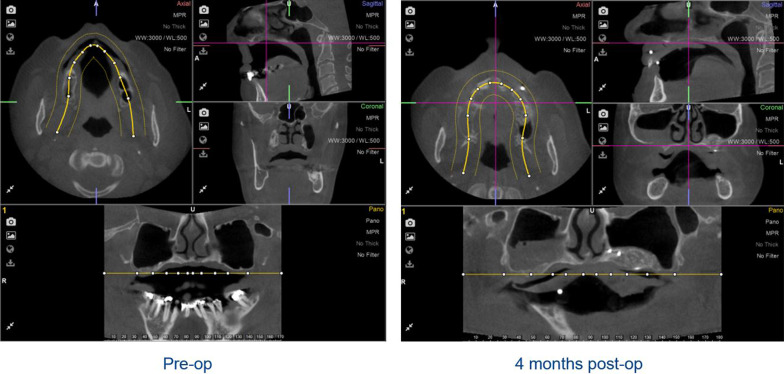

Radiological follow-up with CBCT (iCatVision™ model 17–19, Imaging Sciences International, Hatfield, PA, USA) was applied preoperatively to the maxillary sinus lift procedure, immediately postoperative and 4 months later.

The residual vertical bone height from the preoperative CBCT and the vertical bone gain 4 months after sinus membrane elevation were measured on the radiographic images by two independent researchers (SL and CL) and the average was taken. A protocol for these measurements was made: first the CBCT was uploaded in the 3D-planning program (Nemotec™ 3D Scan Dicom, Madrid, Spain), second the CBCT was positioned in a way that the palate was oriented horizontally in the coronal and sagittal planes and the maxilla was placed in the midline in the transversal plane. The third step was to define the panoramic plane of the maxilla, in this plane the bone heights were measured (Fig. 4).

Fig. 4.

Planes of the preoperative and 4-month postoperative CBCTs in the right orientation: transversal, sagittal and frontal. The lower parts show the defined panoramic plane in which the measurements of bone height were made

In the augmented posterior region of the maxilla, two locations were marked on each side where vertical height measurements were taken. As described previously, the CBCT, 4 months post-augmentation, was used to produce a drilling guide. The sites where the two posterior implants were placed, pre-planned with the implant 3D-planning software, were exactly the sites where bone height was measured. First the bone height in the 4-month postoperative CBCT scan was documented, and afterwards the bone height at exactly this point in the preoperative scan was identified (Fig. 5).

Six months after augmentation all patients showed sufficient new bone formation, which allowed for dental implant placement. The non-augmented and the augmented sides were compared and both showed sufficient new bone formation. However, the non-augmented side showed less opacity suggesting less bone density or less presence of mature bone (see Figs. 4 and 5).